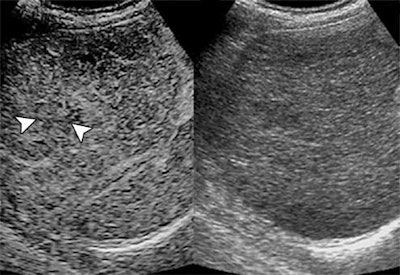

The team found that 31.8% of the nodules became cancerous after a median follow-up time of 26.7 months. And these nodules had a particular sonographic marker: The difference in contrast arrival time between the cirrhotic nodule and the liver on CEUS helped predict eventual cancer conversion risk.

"At initial detection, nodule size and a contrast arrival time difference between the nodule and liver of more than 0.5 second were independent predictors for malignant transformation," Lin's team noted.